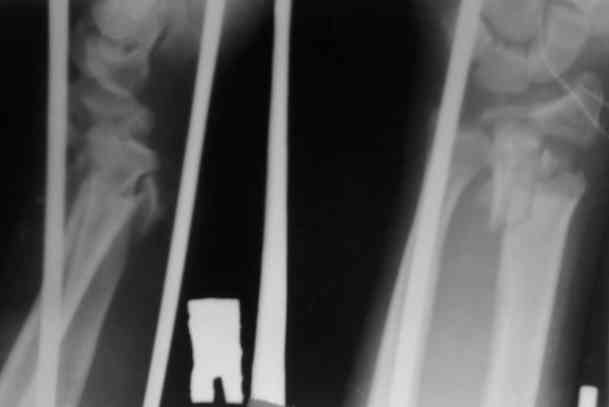

Уважаемые участники форума,поделитесь опытом... Поступил больной 23.03.07 в отделение нейрохирургии с диагнозом:кататравма, ушиб головного мозга ср.тяжести,линейный перелом лобной кости слева, открытые переломы костей обоих предплечий.

По дежурству перооперирован.На оба предплечья наложены ЧД аппараты (см. приложение) Через 3 дня переведен в травм.отделение. Мнения коллег о дальнейшей тактике разделились: накостно с трансплантацией или ЧДО аппаратом Илизарова, с целью добиться, хотя бы относительно удовлетворительного стояния.На сегоднешний день выраженный болевой синдром, больше слева.Раны на предплечье заживают первично.